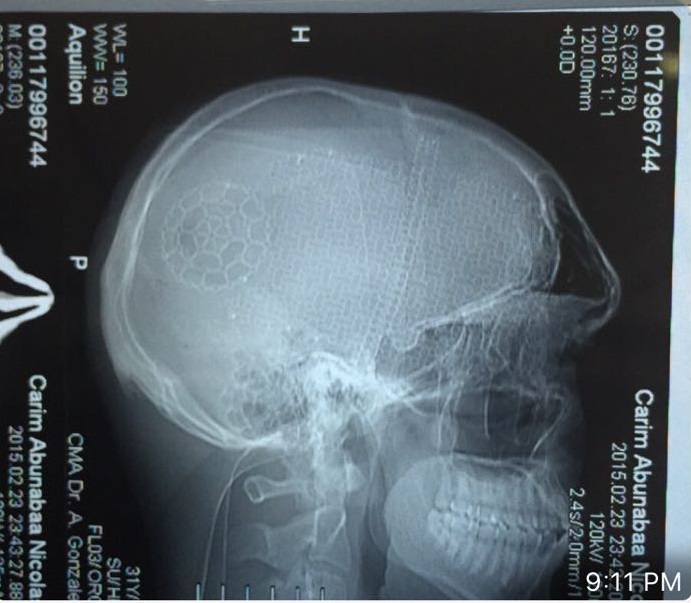

Con el fin de salvaguardar a la población Dominicana del peligro que representa la interacción o contacto con el peligroso discapacitado mental Karim Abu Nabaa, quien goza de impunidad demostrada en República Dominicana de cualquier cosa que haga, gracias a la Relación de su Padre Mustafa Abu Nabaa como los expresidentes Hipolito Mejia, Leonel Fernandez Reyna y Danilo Medina Sanchez, lo que lo han hecho intocable por años. Procedemos a hacer de conocimiento de la Ciudadanía Dominicana las radiografías craneales y el informe neurológico de fecha 25 del mes de septiembre del 2012, realizado por el Neurocirujano Dr. Santiago Valenzuela Sosa, los que podrán ser descargados mas abajo.

En dicho informe el profesional de la medicina expone, entre otras cosas, que el discapacitado mental Karim Abu Nabaa tiene: «Baja tolerancia al stress emocional, reaccionando con extrema irritabilidad y hasta violencia cuando se considera mal tratado o se le desagrada. Al analizar su Resonancia Magnetica Cerebral del 4 de Septiembre del 2012 comprendemos por que de estos trastornos neurologicos;»

Por esta razón reiteramos nuestra advertencia a la población ya que este a pesar de aparentar ser una persona normal, en realidad no lo es y padece de una grave lesión cerebral, tal y como en el mismo informe neurológico del Dr. Santiago Valenzuela Sosa donde también se expreso: «En total, consideramos que Karim Abunaba Nicolas debe ser visto como un paciente Neurológico en constante vigilancia medica debido a sus deficiencias funcionales y su epilepsia.»